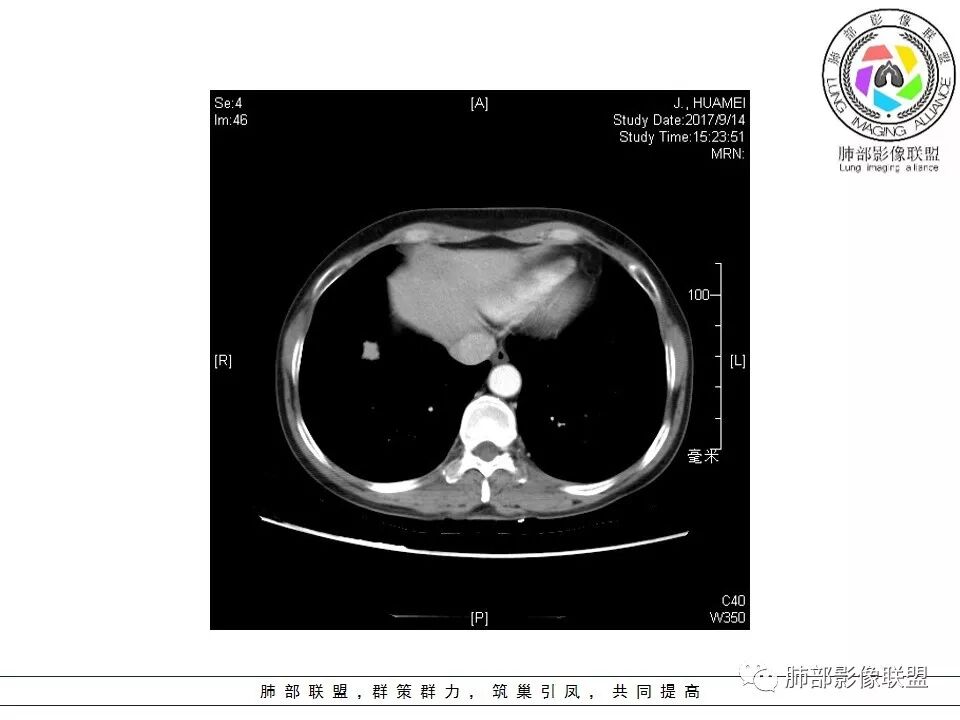

晨读:右肺下叶肿块影,浅分叶,不均匀强化,有血管穿行其中,考虑肺癌,神经内分泌肿瘤可能性大。

右肺下叶结节,边缘毛糙,内支气管推移,有血管贴行,小细胞肺癌?

晨读:右下肺前基底段支气管亚段分叉处占位,密度均匀、中度均匀强化,结节近边缘有支气管、血管穿行,结节边缘较光滑、有细短毛刺、无分叶,结节周围无卫星灶。考虑:PSP,鉴别:小细胞肺癌、不典型错钩瘤

右肺下叶前基底段肿块,边缘不光滑,毛糙,内见充气支气管征,边缘有浅分叶,肿块周围无病灶,排除了结核。增强扫描明显强化,内见血管影,考虑恶性肿瘤。女性,腺癌多见。

晨读:右肺下叶肿块影,浅分叶,边界清,轻度均匀强化,血管自然穿行,NSE偏高,考虑小细胞肺癌!

中年女性,右肺下叶前基底段肿块,轻度分叶,有棘样突出,充气支气管征穿行并形成脐凹征。增强扫描中度强化,内见血管影,血管壁毛糙,考虑恶性,腺癌?小细胞肺癌?

晨读,右肺下叶前基底段实性结节,边缘膨隆,可见多发浅分叶,结节内密度均匀,增强后呈轻度均匀强化,血管穿行走形自然,首先考虑恶性肿瘤,内有支气管穿行,淋巴瘤可能大,腺癌待排。

右肺下叶肿块,边缘光滑,浅分叶,膨隆明显,局部有清楚的ggo,考虑恶性,类癌首可能,鉴别腺,PSP。

中年女性,右下类圆形肿块,部分膨胧,边缘浅分叶,脐凹,内见血管穿行,增强轻中度强化,叶间胸膜结节?考虑腺癌,内有支气管穿行,鉴别淋巴瘤。

右肺下叶肿块影,边缘光滑,彭隆,浅分叶,内见支气管通过,增强明显强化,内见血管影,考虑恶性肿瘤,神经内分泌癌,鉴别淋巴瘤。

中年女性,体检发现,病史及化验无特殊。胸部CT右肺下叶前基底段见一类圆形结节,边界清楚,分叶不明显,边缘呈锯齿状改变,病灶内支气管穿行,无扩张及扭曲,增强扫描病灶明显均匀强化,内见穿行血管影,走形无扭曲。考虑粘膜相关性淋巴瘤可能。鉴别炎性假瘤、腺癌及小细胞癌。

患者中年女性,因“体检发现右下肺占位4天。”入院,肿瘤标记物NSE轻高。

胸CT:右肺下叶前基底段占位性病变,内可见支气管穿过,病灶边缘不规则,呈浅分叶,未见明显毛刺。纵隔窗可见病灶密度相对均匀,增强可见病灶强化,内可见血管增粗,边缘模糊,总体考虑恶性,腺?。良性疾病鉴别错构。

右下肺类圆形实形结节,边缘膨隆,浅分叶,其内可见支气管及血管影走行,轻度强化,考虑恶性病灶,淋巴瘤?类癌?

边缘彭隆,还是考虑肿瘤,支气管通入,肺内原发,支气管自然穿行稍扩张,血管比较自然同行,漂浮征,增强后整个比较均匀无明显坏死,淋巴瘤首选。恶性应该没有问题,建议穿刺。